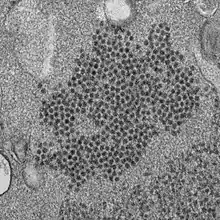

| Enterovirus D68 particles | |